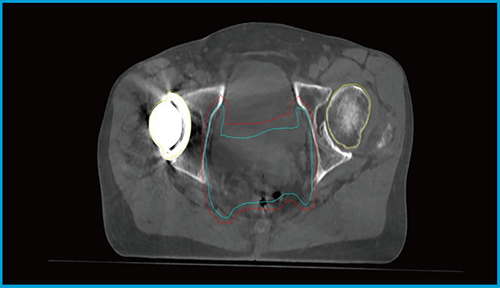

また, CBCT画像再構成にメタルアーチファクト低減(MAR)アルゴリズムが搭載されたことも大きなメリットである。このMARアルゴリズムは,骨盤内に留置される金マーカーのような小さな金属だけでなく,人工骨頭の金属インプラントから発生するアーチファクトも大幅に軽減することが可能となる。従来のCBCTでは,金属アーチファクトが広範囲にわたって発生し,標的や周囲の臓器が不明瞭になり十分な画像照合が困難であったが,HyperSight CBCTではSim-CTとほぼ同等の鮮明な画像が取得でき,正確な画像照合が可能となった。

図3に,人工骨頭を含む骨盤領域のHyperSight CBCTを示す。明瞭な画像による位置照合により,標的の正確な線量担保と,小腸など周囲の正常組織への線量を最小限に抑えることができ,急性期および晩期合併症のリスク低減が図れると期待できる。

図3 金属インプラント(人工骨頭)が挿入された子宮頸がんにおけるIMRT実施時の HyperSight CBCT画像(ストラクチャー含む)